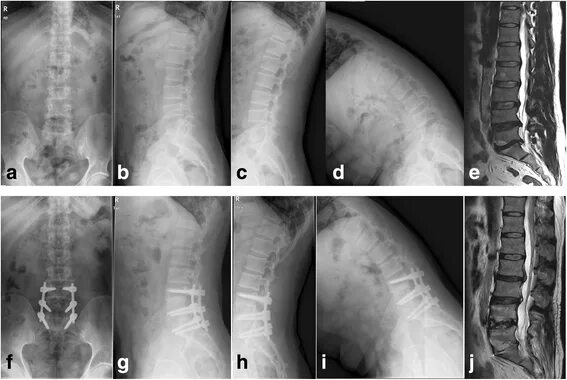

Дегенеративно дистрофические изменения дисков l5 s1